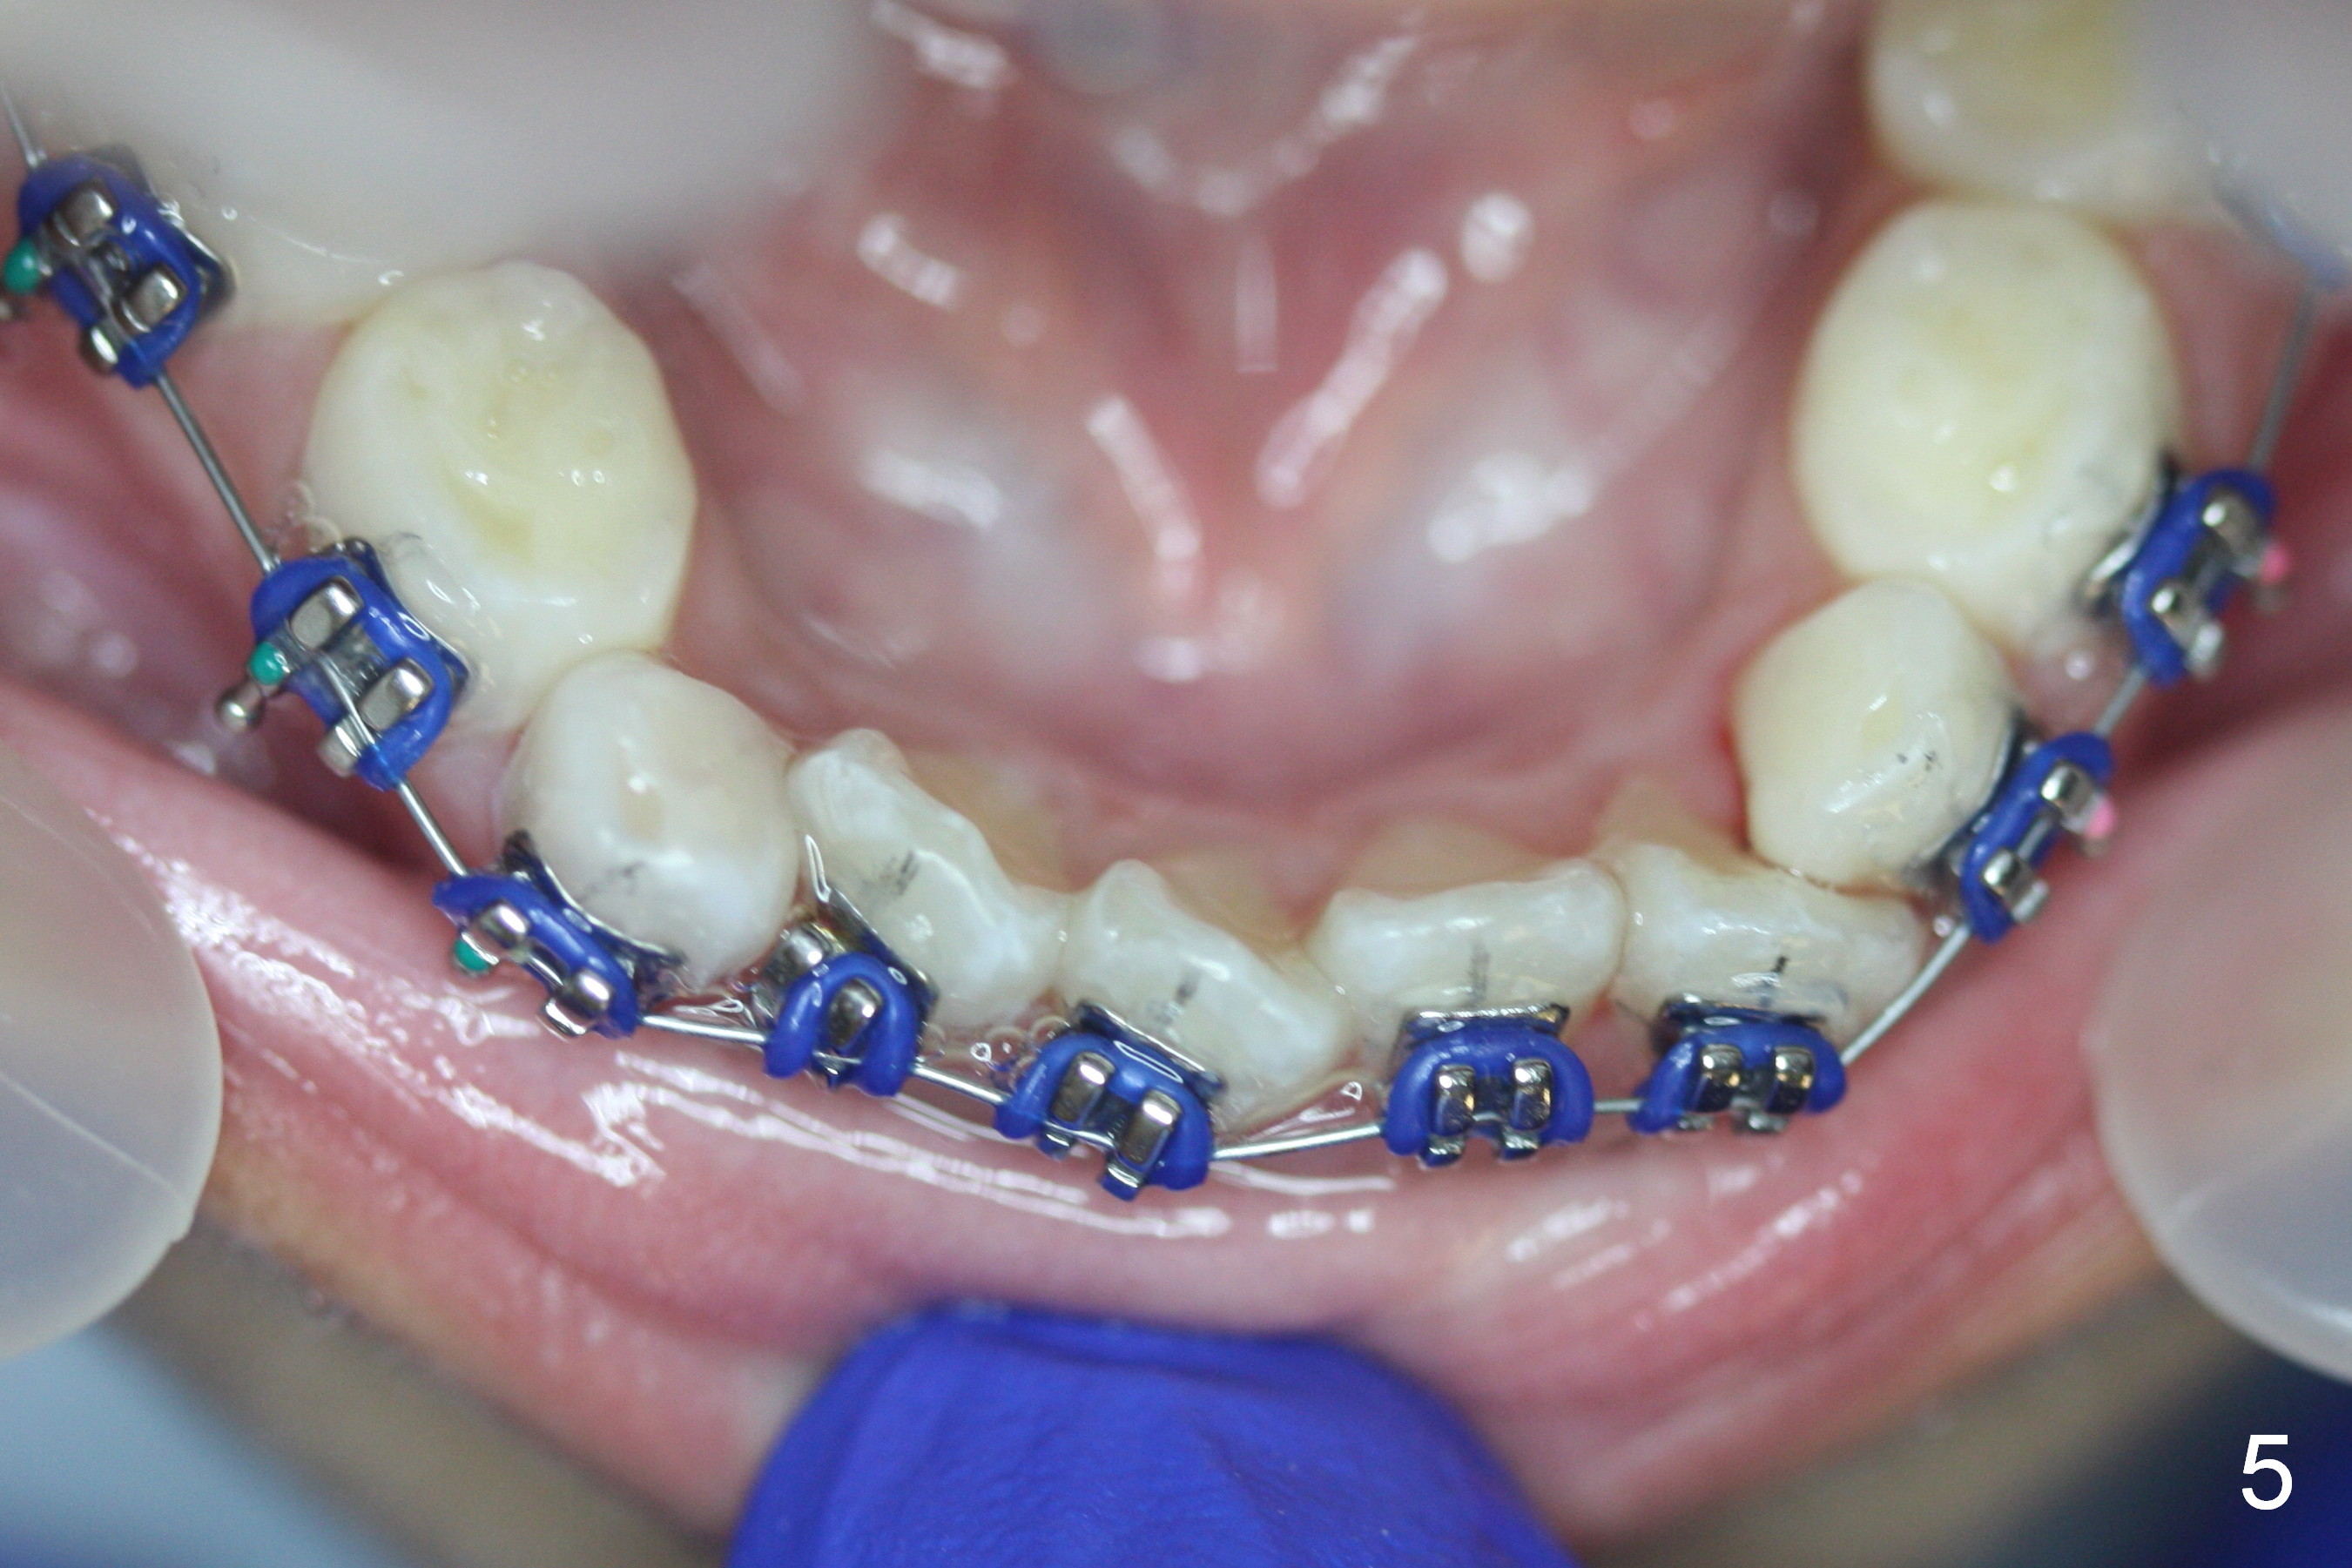

The 2nd visit post bracketing, the lower brackets are placed (Fig.5). The cross bite is still not completely fixed (Fig.6).